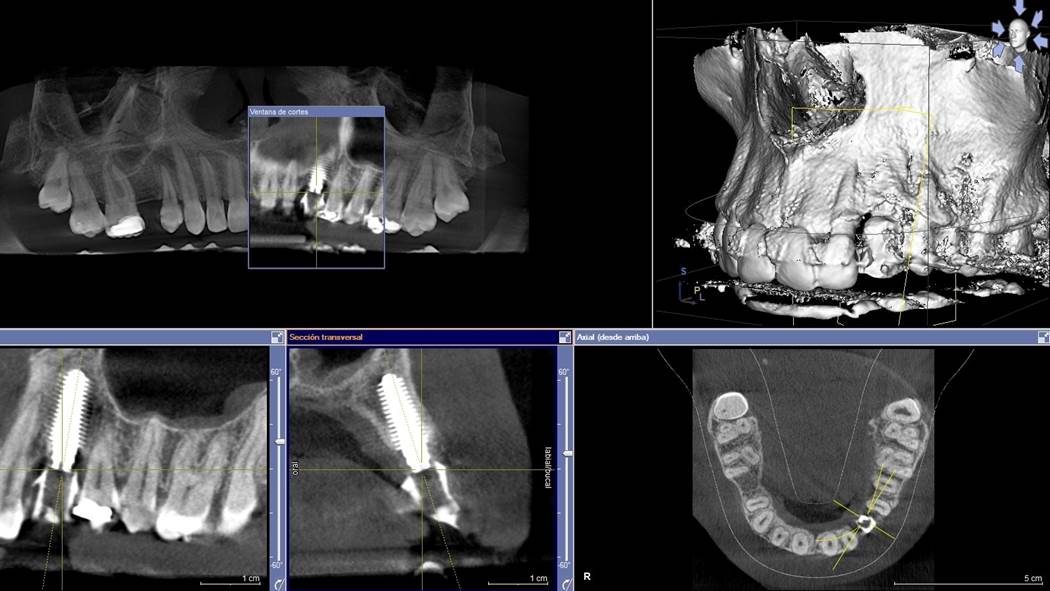

Clinical case: Digital Data Save concept in upper jaw premolar area

- Courtesy of Dr. Lysov Alexander Dmitrievich & Dr. Sofronov Matvey Vitalievich, Russia -

Keywords

AnyRidge, R2GATE, R2GATE guide, ISQ value, initial stability, immediate loading, KnifeThread, maxillary posterior, #14, Digital, Dr. Lysov Alexander Dmitrievich, Dr. Sofronov Matvey Vitalievich, zirconia abutment, CAD/CAM crown

“AnyRidge & R2GATE show stable results

after immediate extraction, immediate implant placement, & immediate loading,

even with low bone density.”